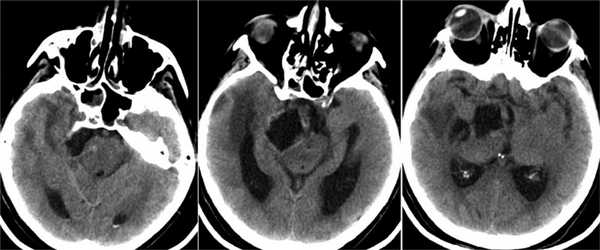

Пациент Х., 62 лет. Начиная с 2002 г. отмечал постепенное развитие птоза с двух сторон, нарастание двоения предметов перед глазами. В 2009 г. при амбулаторном обследовании в НМИЦ нейрохирургии им. Н.Н. Бурденко выявлено двустороннее поражение глазодвигательных нервов: справа резко выраженный полуптоз — ширина глазной щели не более 5 мм; слева почти полный птоз — ширина глазной щели не более 2—3 мм; резко выраженное паралитическое расходящееся косоглазие, движения глаз отсутствуют во всех направлениях, анизокория; справа зрачок средней ширины, реакция на свет отсутствует, слева умеренный мидриаз, фотореакция отсутствуют, кератит слева (рис. 4). Рис. 4. Клинический случай 2. Глазодвигательные нарушения у больного с двусторонней невриномой глазодвигательного нерва. Внешний вид больного: двусторонний выраженный полуптоз (а); расходящееся паралитическое косоглазие, левосторонний кератит (б). По данным МРТ головного мозга выявляются два узла опухоли неправильной округлой формы в области цистернальных сегментов обоих глазодвигательных нервов (рис. 5). Рис. 5. МРТ головного мозга пациента Х. (режим Т1 с контрастным усилением, фронтальная и аксиальная проекции): определяются 2 узла опухоли цистернальных сегментов обоих глазодвигательных нервов. Клинических проявлений болезни Реклингаузена не было. От предложенного хирургического лечения пациент отказался. Его дальнейшая судьба неизвестна.